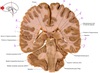

37

a

body of fornix

38

b

Septum pellucidum

39

c

Body of corpus callosum

40

d

Body of lateral ventricle

41

e

Body of caudate nucleus

42

f

Posterior limb of internal capsule

43

g

Putamen

44

h

Tail of caudate nucleus

45

i

Interpeduncular fossa

46

j

interthalamic adhesion

47

k

Inferior horn of lateral ventricle

48

L

Hypothalamus

49

m

Corona radiata